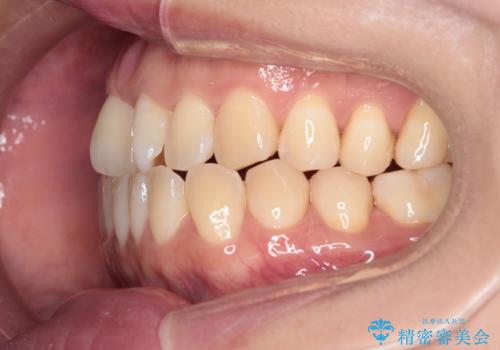

【インビザライン】前歯の捻れ気になる

- 上の前歯の捻れを主訴に来院されました。

前歯の捻れとがたつきを改善するために、IPR(歯と歯の間を削る処置)と歯列拡大をすることで歯並びを整えていく治療計画を立てました。

かみ合わせを整えるためにゴム掛けも行いながら、治療していきました。

患者様にマウスピースの使用とゴム掛けを頑張っていただいたおかげでリファイメント(マウスピースの再発注)も1回で終了することができました。